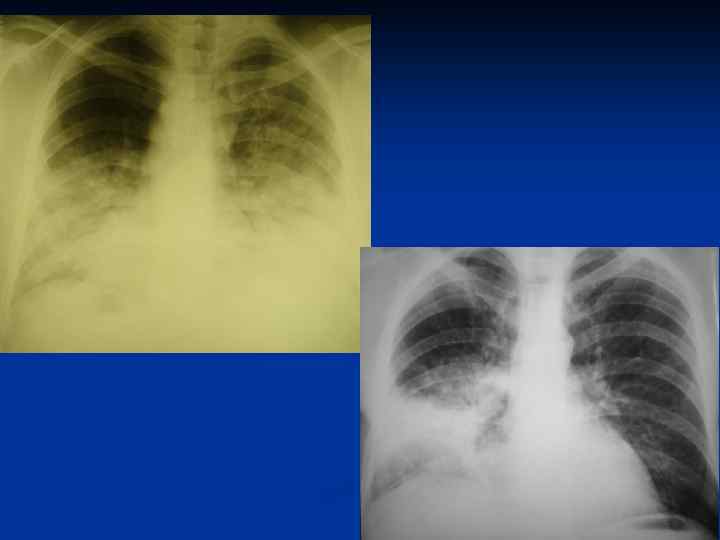

Рентгенография грудной клетки в прямой проекции 7

35 -летняя женщина с микоплазменной пневмонией и нормальной рентгенограммой (слева). На РКТ – множественные очаговые уплотнения в верхней доле правого легкого (справа) 8